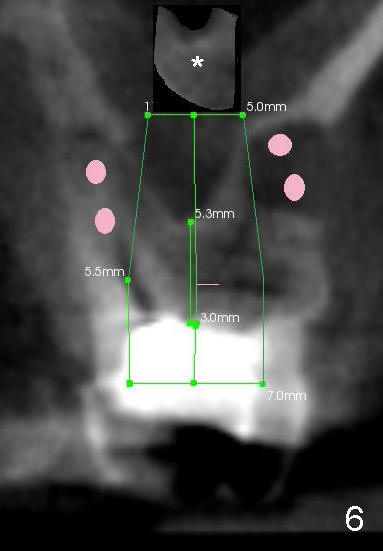

Ultimately, an implant as large as 7x14 mm is placed (Fig.6 green area). Its apical portion is covered by the lifted bone (*, although maybe thin due to continuous compression), whereas the side of the apical portion of the implant contacts the original socket walls (i.e., the side of the inferior extension of the sinus floor). In all, the contact area of the implant is expected to increase; so will be the insertion torque. No bone graft is needed over the sinus lift, while it may be placed in the sockets (pink circles).